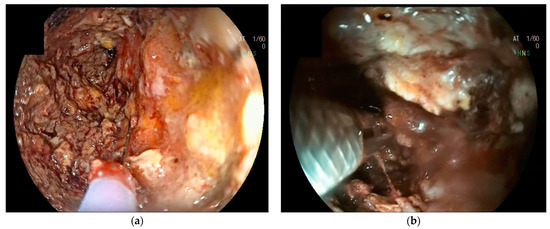

10. Direct Endoscopic Necrosectomy